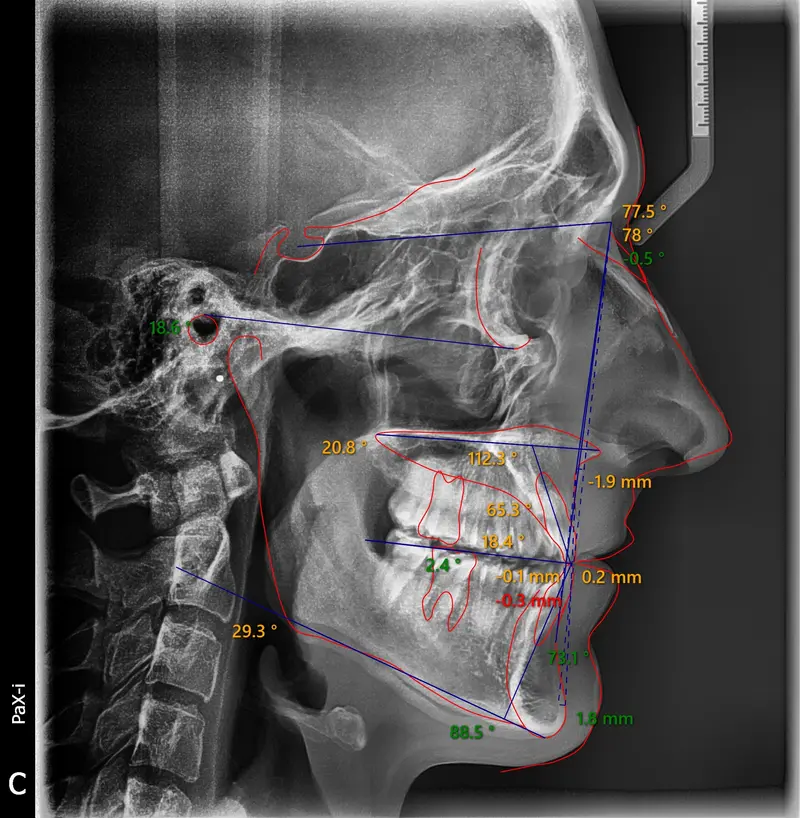

The Diagnosis

Bimaxillary protrusion (teeth flaring forward) causing lip incompetence. The patient struggled to close his lips comfortably, straining the chin muscle (mentalis).

The Engineering

A strategic extraction plan (4 premolars) allowed us to retract the front teeth. Note the dramatic improvement in chin projection and facial balance. The extractions did not flatten the face; they harmonized it.